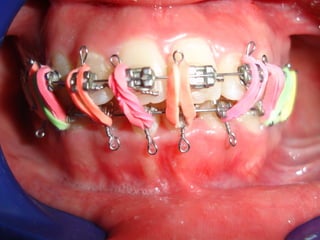

Eliminación de rotaciones. Correcciónde las discrepancias de longitud de arco. Posición de los incisivos y molares por medio del torque adecuado. Llevar cualquier otra alineación en el arco. Eliminación de rotaciones. Corrección de las discrepancias de longitud de arco. Posición de los incisivos y molares por medio del torque adecuado. Llevar cualquier otra alineación en el arco.

Evita el potencialde recidiva Aumenta la velocidad y eficacia del tratamiento